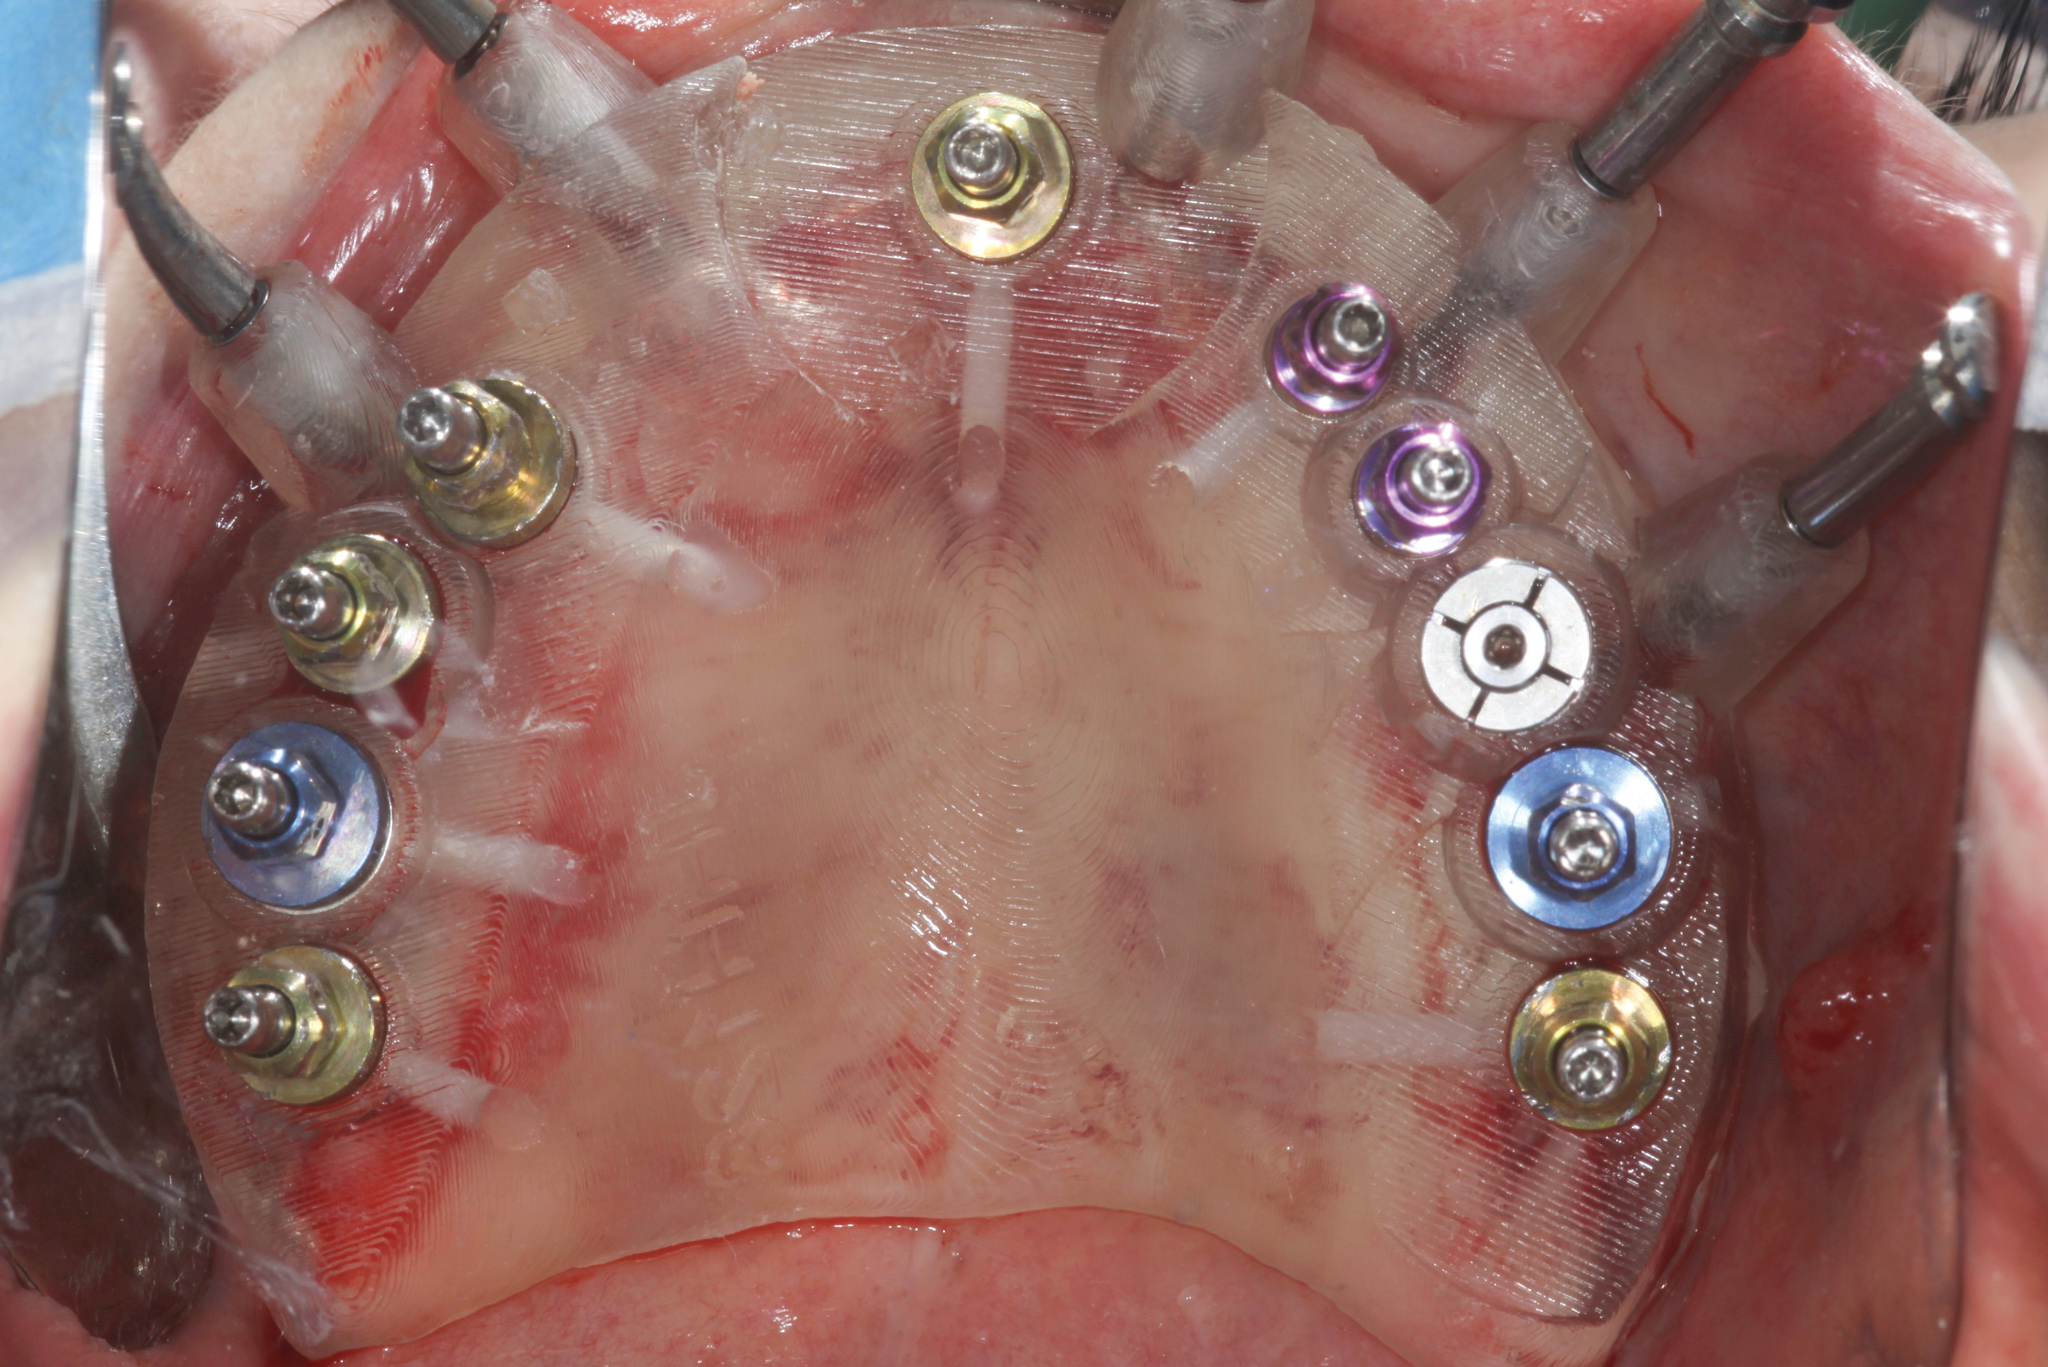

Fig 9. CT guided surgery planning. Ten implants were planned, including a maxillary anterior implant to be placed in the anterior nasal spine.

Figure 9

Fig 10. Fully guided, flapless implant placement.

Figure 10